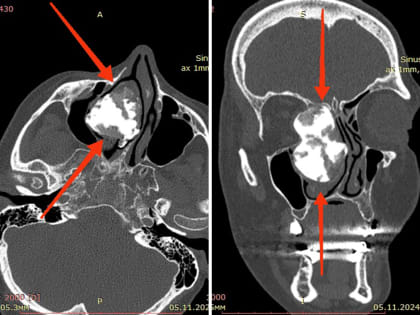

ЛОР-врачи Ростовской областной клинической больницы удалили из полости носа опухоль размером с киндер-сюрприз.